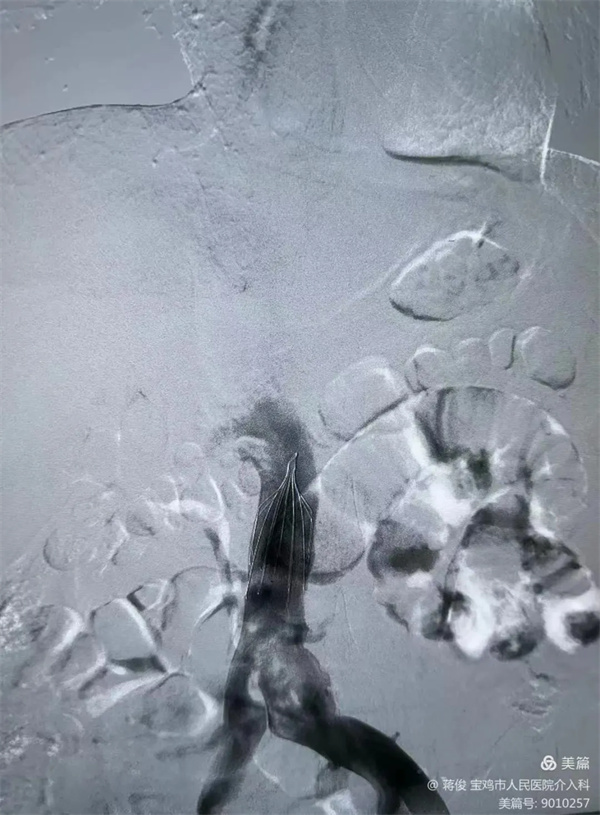

下肢靜脈DSA造影提示大量新鮮血栓

3.webp.jpg

肺動脈DSA造影提示肺動脈主干及分支大量血栓,予以肺動脈造影、血栓溶解、肺動脈碎栓